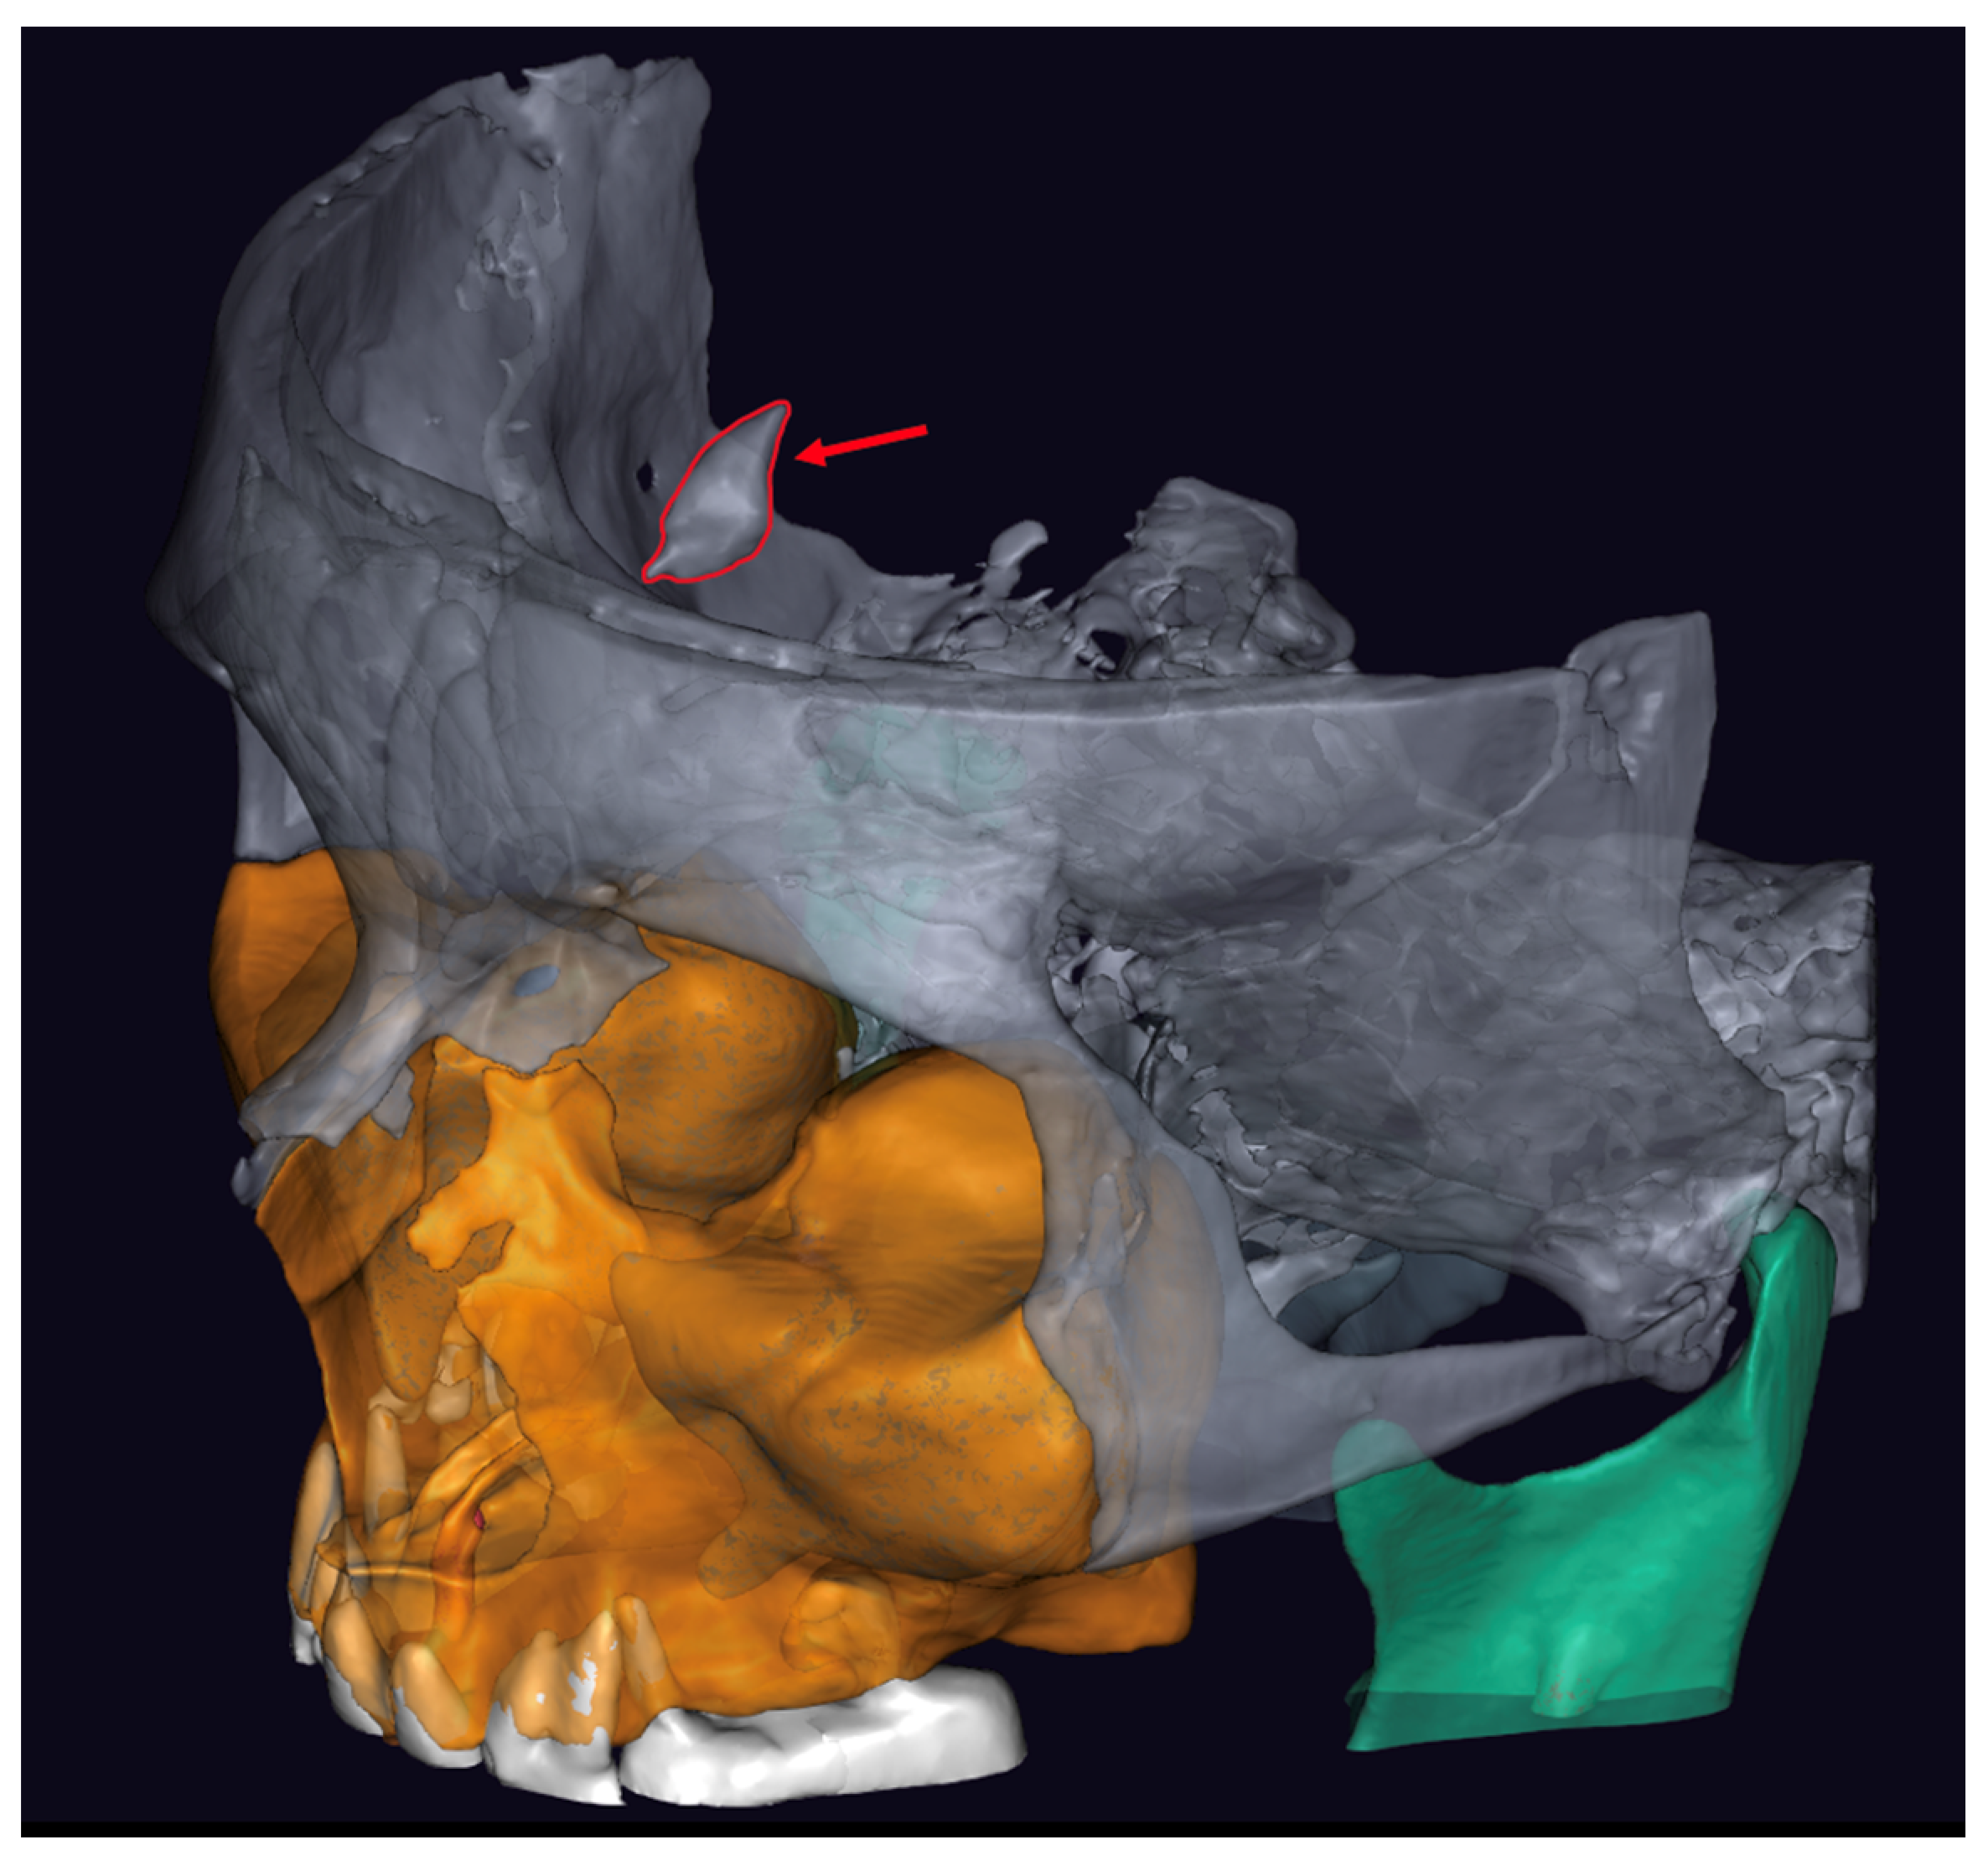

2. Case Report and AI Application